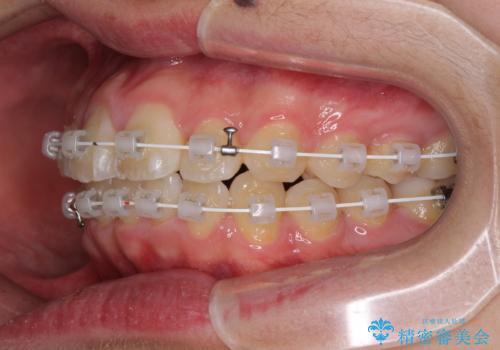

前歯のデコボコを短期間で治療 目立たないワイヤー矯正

- 矯正装置

- 審美装置

- 上下前歯のデコボコを改善したいとのことで来院された患者様です。

自己管理を減らしたいとのことで、ワイヤー装置による矯正治療を行うこととしました。

中学生と言うこともあり、1年強の短期間で終了しました。

歯磨きがしっかりとできないと虫歯になるリスクがありましたが、治療期間中は清潔な状態を保っていただけました。